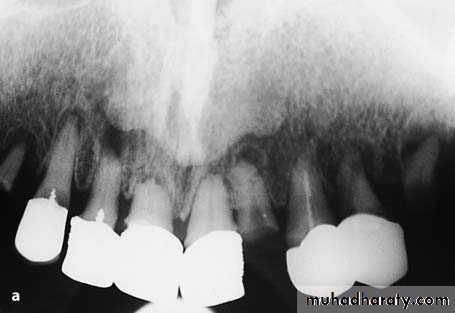

a Radiograph of maxillary teeth, after whose removal smoothing of alveolar bone is required. b Clinical photograph of teeth to be extracted

Diagrammatic illustration (a) and clinical photograph (b) of gross intraseptal irregularities after multiple tooth extractions